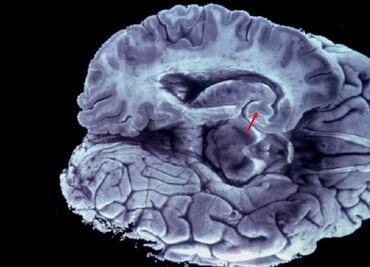

El dispositivo consta de un electrodo a nivel encefálico; una extensión debajo de la piel y el neuroestimulador que se implanta en la clavícula